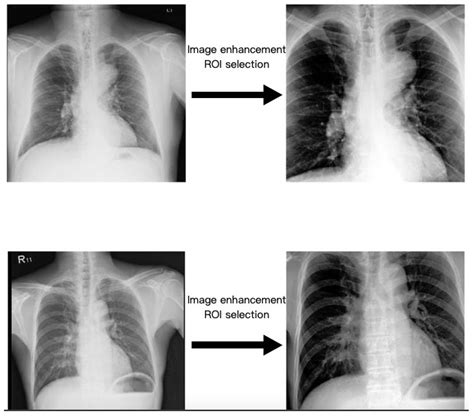

One of the most challenging aspects of Thoracic Aorta Ectasia is that it is frequently asymptomatic in its early stages. Many patients are diagnosed incidentally during a routine chest X-ray or CT scan for an unrelated issue. However, as the dilation progresses, some individuals may experience:

How Doctors Diagnose Ectasia

Because symptoms are often absent, imaging is the gold standard for diagnosing and tracking the progression of aortic dilation. Physicians rely on several non-invasive tests to evaluate the size and shape of the aorta: